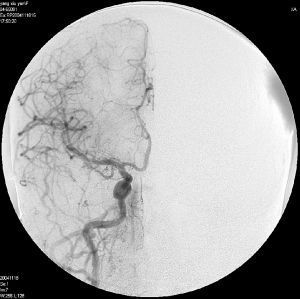

1895年,德國物理學(xué)家Roentgen發(fā)現(xiàn)X射線,為放射診斷與治療學(xué)及介入放射學(xué)形成和發(fā)展奠定了基礎(chǔ)。隨后血管造影術(shù)僅作為一種新奇而冒險的診斷技術(shù)偶被應(yīng)用于臨床診斷和基礎(chǔ)研究,直至1953年瑞典醫(yī)師Sven- Ivar Seldinger發(fā)明套管針-導(dǎo)絲-導(dǎo)管穿刺法,血管造影技術(shù)才被逐漸廣泛認(rèn)可和應(yīng)用,與此同時“介入放射學(xué)”概念逐步孕育。1963年,美國醫(yī)師Dotter等[1]首次提出利用非外科性技術(shù)在進(jìn)行影像診斷的同時治療疾病的設(shè)想,并且在1964年首次采用同軸導(dǎo)管技術(shù)對下肢動脈狹窄患者成功進(jìn)行擴(kuò)張治療,改善了血液循環(huán),緩解了下肢缺血癥狀,這成為現(xiàn)代介入醫(yī)學(xué)理論和實(shí)踐的奠基石。1967年,Margulis[2]在美國放射學(xué)雜志上最早提出“Interventional Diagnostic Radiology”,即“介入診斷放射學(xué)”概念,而“InterventionalRadiology”,即“介入放射學(xué)”概念是1976年由Wallace等[3]在《Cancer》雜志上正式提出。

介入放射學(xué)于20世紀(jì)70年代末傳入中國,我國老一輩介入放射學(xué)家林貴、劉子江等在設(shè)備及器械落后情況下,克服困難,不惜犧牲個人健康,為中國介入放射學(xué)發(fā)展拉開序幕。1979年,榮獨(dú)山和林貴[4]報道針對原發(fā)性肝癌肝動脈造影的研究;1982年,劉子江受國家衛(wèi)生部委托首次在貴陽醫(yī)學(xué)院放射科舉辦衛(wèi)生部介入放射學(xué)學(xué)習(xí)班,培養(yǎng)了我國最早一批介入放射學(xué)工作者。從此星火燎原,介入放射學(xué)在中國大地蓬勃發(fā)展。1986年,在山東濰坊召開第一屆全國介入放射學(xué)學(xué)術(shù)會議,自此開始了我國介入放射學(xué)日新月異的學(xué)術(shù)交流。1990年,衛(wèi)生部下發(fā)《關(guān)于把一部分有條件開展介入放射學(xué)的放射科改為臨床科室的通知》,從管理體制上確立了介入放射學(xué)的作用和地位,一些大醫(yī)院相繼成立介入病房或獨(dú)立設(shè)置的介入科及介入研究室等,從而進(jìn)一步促進(jìn)了

20世紀(jì)90年代,由于大批海外學(xué)者回到國內(nèi),以及國內(nèi)外頻繁的學(xué)術(shù)交流,我國與先進(jìn)國家間介入診療技術(shù)差距逐步縮小。1988年,李彥豪等[5]首次報道下腔靜脈膜性狹窄型布-加綜合征球囊擴(kuò)張治療。1991年,徐克等首次報道下腔靜脈節(jié)段閉塞型布-加綜合征介入治療。1992年,徐克等完成了國內(nèi)首例經(jīng)頸靜脈肝內(nèi)門體靜脈分流術(shù)(TIPS),并于1994年在《中華放射學(xué)雜志》發(fā)表首篇TIPS臨床應(yīng)用文章[6]。從此,我國介入放射學(xué)領(lǐng)域新人輩出,并在心臟、神經(jīng)、血管和非血管介入領(lǐng)域不斷涌現(xiàn)出新的技術(shù)。我國第一個介入專業(yè)刊物《介入放射學(xué)雜志》也誕生于1992年,由陳星榮和林貴共同創(chuàng)立。